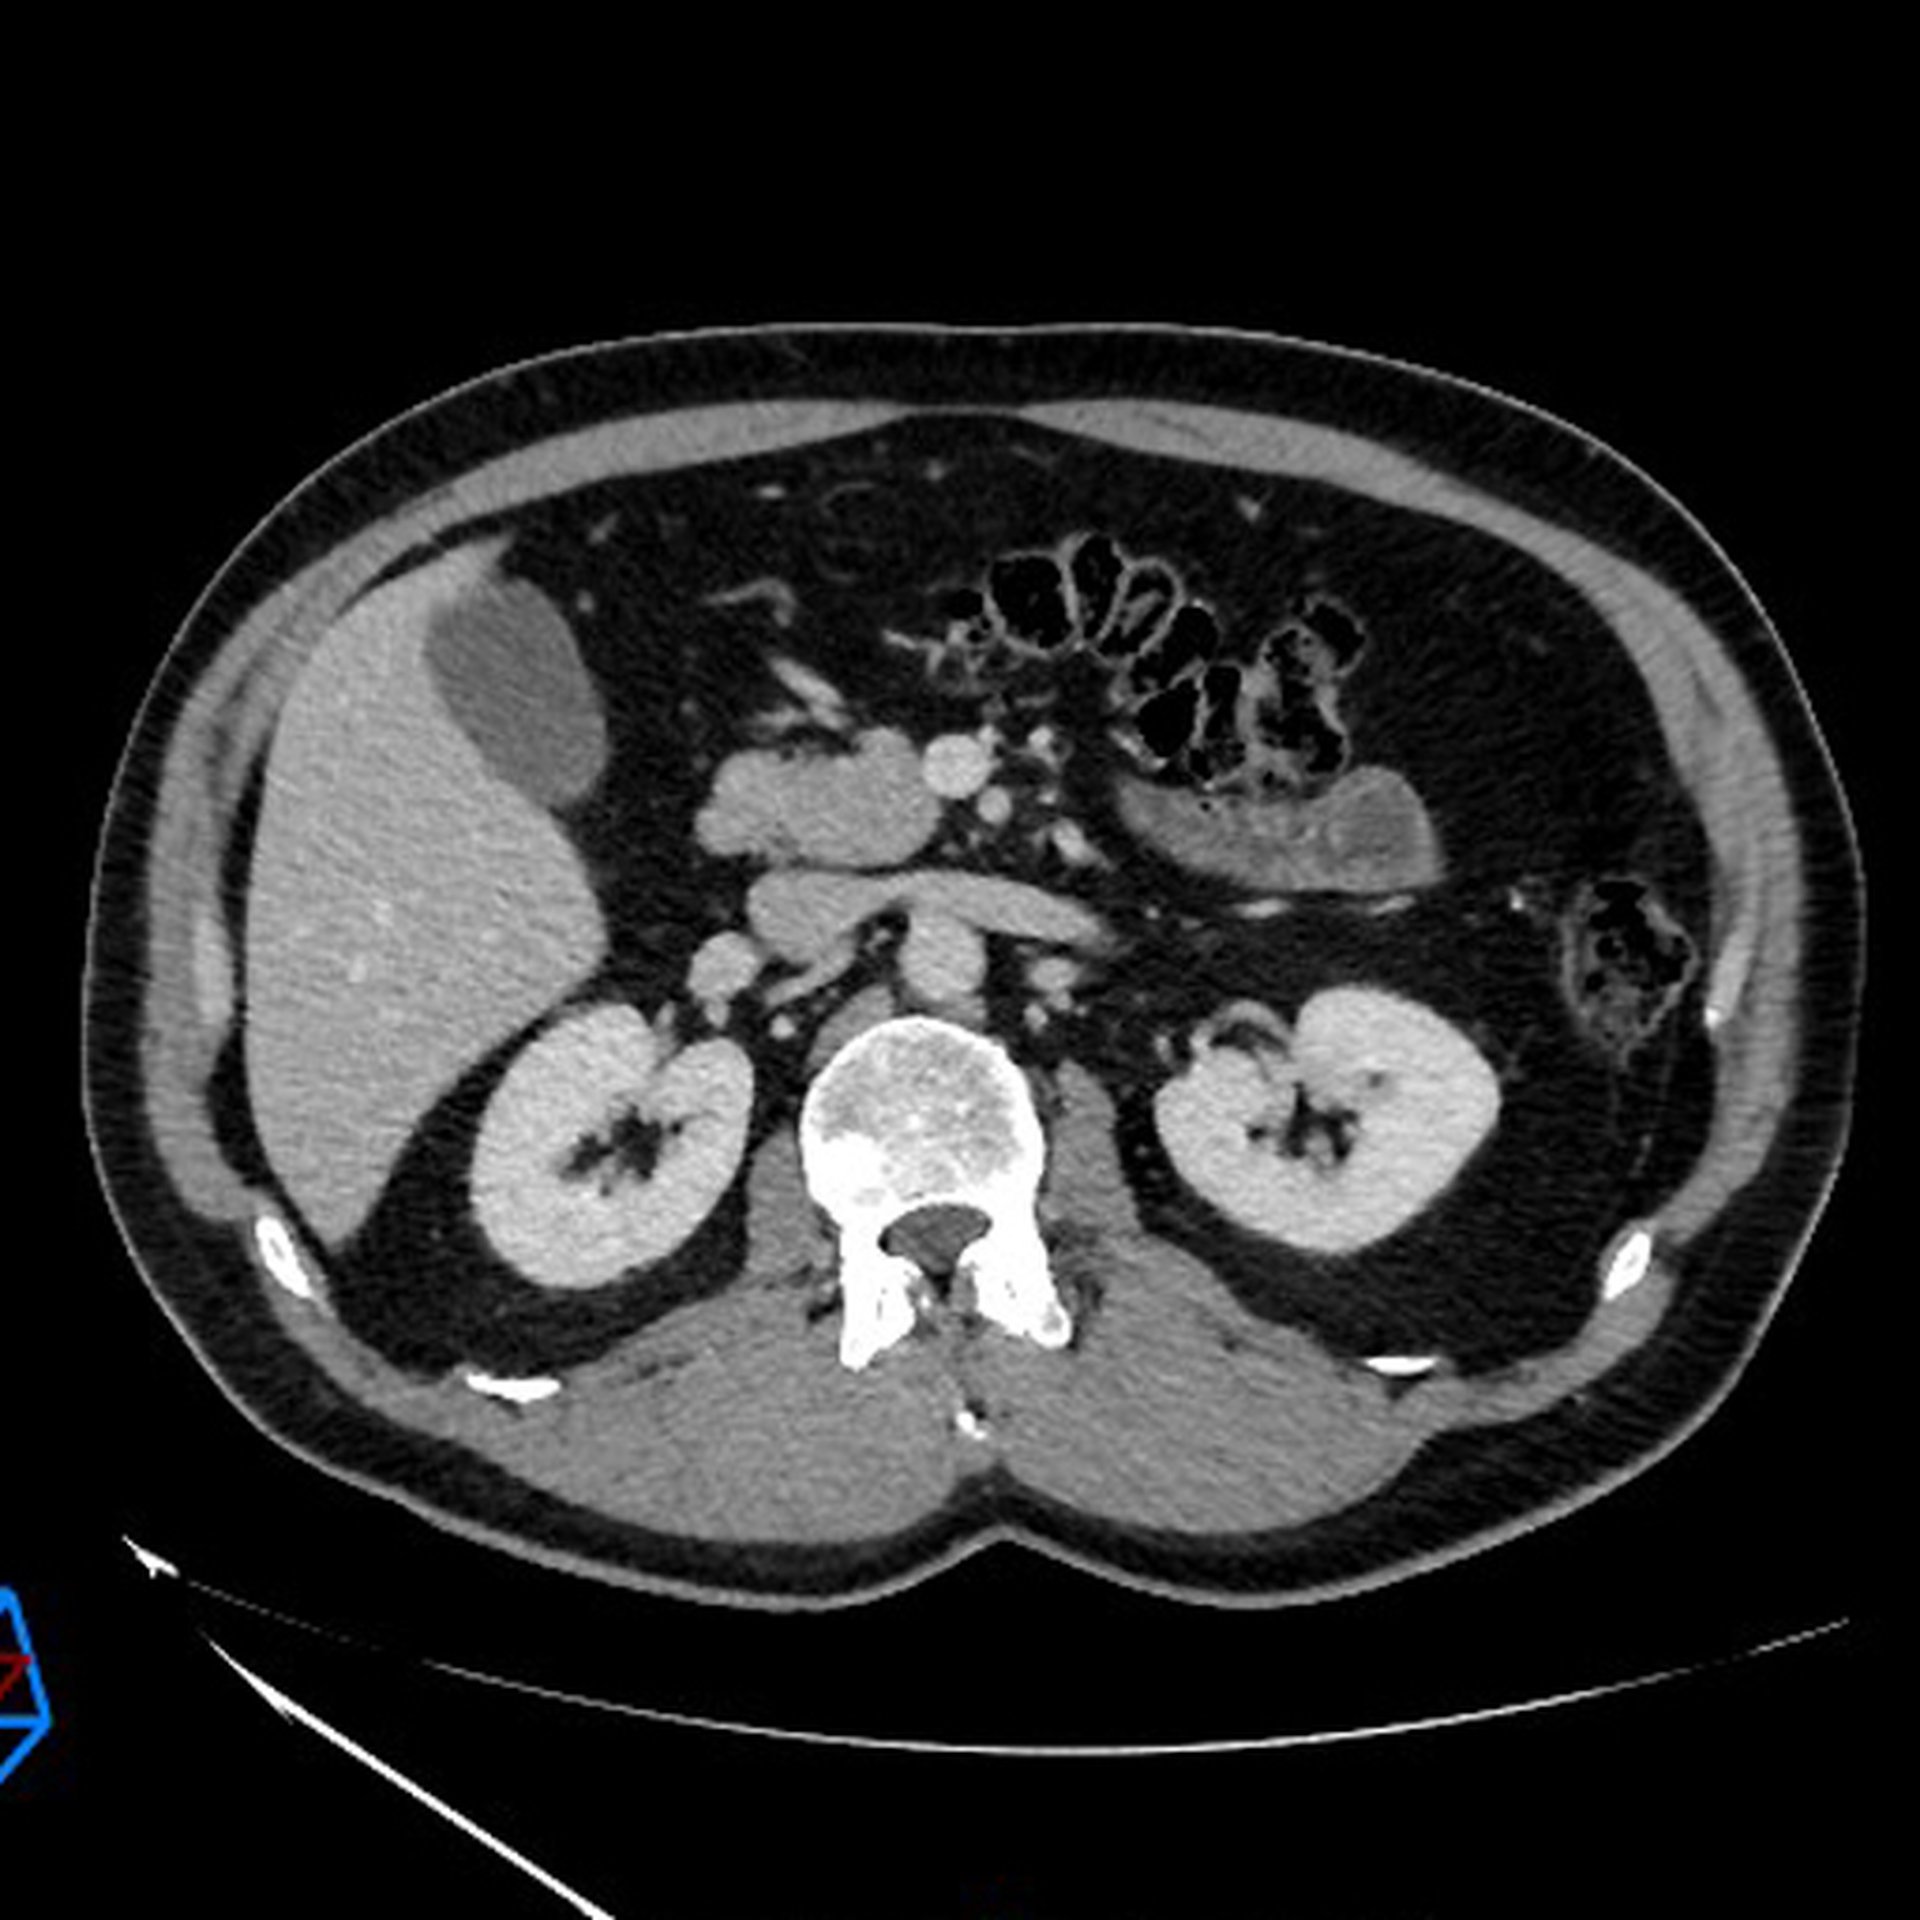

Comme pour les examens radiographiques standard, le scanner ou tomodensitométrie utilise les rayons X. Les radiologues et manipulateurs en radiologie qui réalisent vos examens contrôlent parfaitement la dose de rayonnement nécessaire à la réalisation de votre examen.

La dose est optimisée en fonction de l’indication de l’examen, du protocole à réaliser et de votre morphologie. La dose d’irradiation est inscrite dans votre compte rendu d’examen (DLP, exprimée en mGy.cm). Cette technique d’imagerie permet d’explorer l’ensemble du corps humain, en coupes millimétriques et obtenir des reconstructions dans les 3 plans de l’espace et des reconstructions volumiques qui seront transmises dans votre dossier (images et CD).

Le protocole d’examen est adapté selon les organes étudiés et la pathologie recherchée. Certains examens nécessitent parfois une injection intra‑veineuse de produit de contraste iodé pour l’étude de l’abdomen, du thorax, des vaisseaux et de l’appareil urinaire essentiellement.